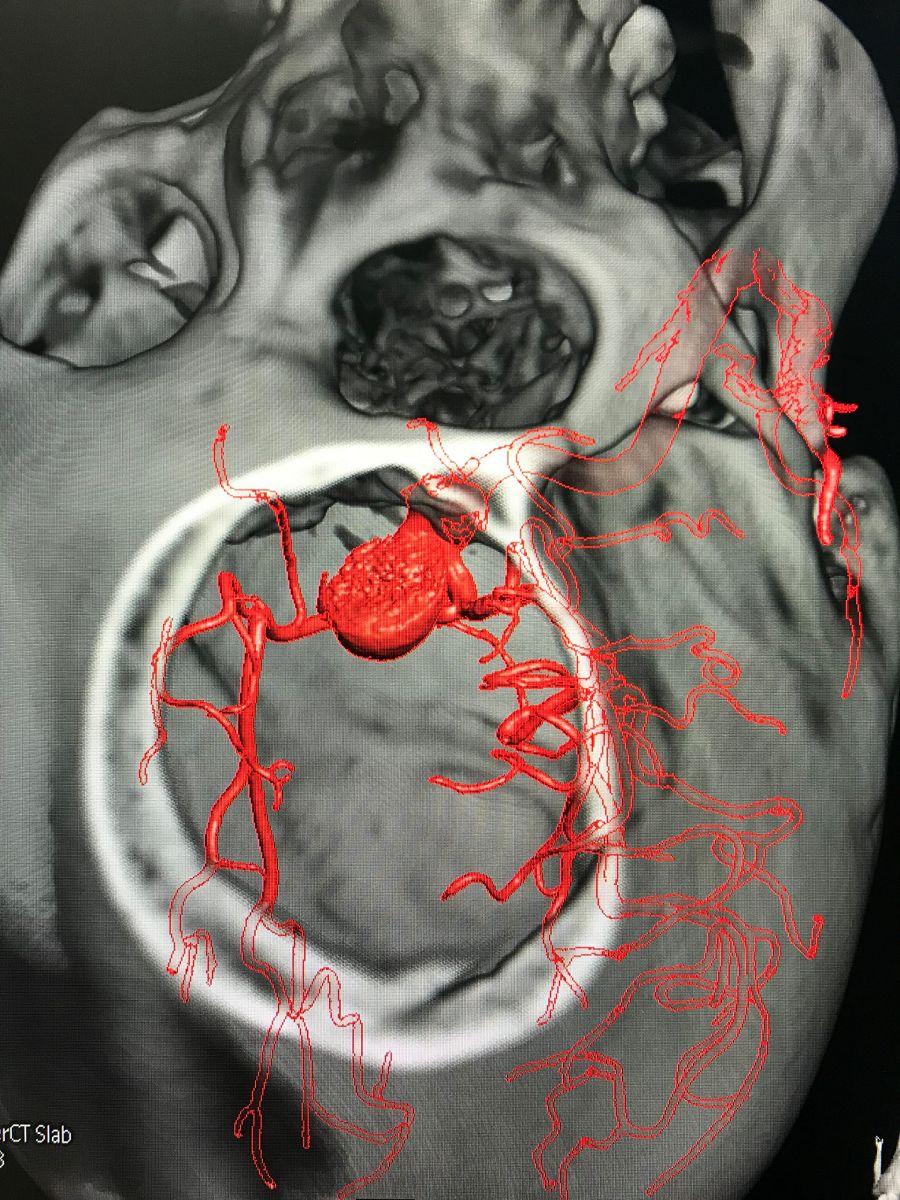

入院后完善DSA检查提示颅内多发动脉瘤:右侧颈内动脉眼段大动脉瘤(约18*19mm,瘤颈6.6mm),左侧眼动脉段及床突段动脉瘤。和家属沟通病情,告知介入和开颅手术风险利弊后,患者家属选择开颅动脉瘤夹闭手术治疗。进一步行DSA+CT融合,模拟手术入路视角。

术前MRA和CTA

右侧眼动脉瘤

左侧眼动脉段及床突段动脉瘤

术前融合后模拟开颅骨窗

术前融合后模拟显微镜视角